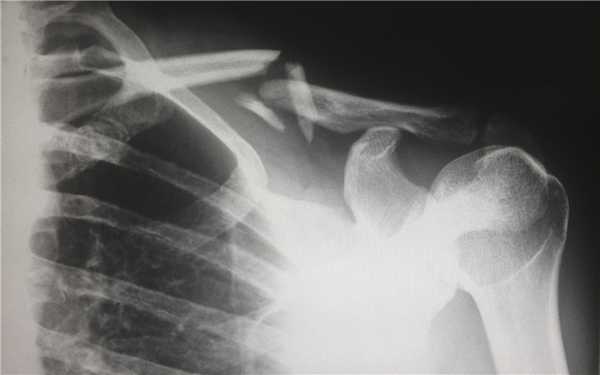

Компьютерная томография (КТ, или МСКТ) является наиболее информативным методом визуальной оценки посттравматических изменений костей, суставов и окружающих тканей. В отличие от других видов лучевой диагностики, при КТ тело человека сканируется поперечно тонкими срезами, на сканах визуализируются ткани различной морфологической структуры (кости, внутренние органы, системы кровообращения и лимфотока), а на основании полученных изображений создается трехмерная модель-реконструкция исследуемой части тела и сканы в трех плоскостях.

Таким образом, будучи пространственным, а не плоскостным (как рентген) методом визуализации любых костных анатомических структур, КТ позволяет достоверно определить тип травмы, увидеть возможные осложнения и повреждения соседних тканей. Поэтому среди врачей это исследование считается предпочтительным для диагностики переломов, особенно осложненных, в том числе внутрисуставных, не рутинных. Плюсом КТ также является оперативность и простота обследования для пациента.

Зачем делать КТ при переломе?

Компьютерная томография позволяет детально визуализировать кости, суставы и окружающие ткани в режиме 3D, что делает этот метод идеальным для диагностики переломов разной степени сложности. Врач-рентгенолог увидит даже небольшое смещение костей, сколы и трещины, а также сможет точно рассчитать любые отклонения с помощью программного обеспечения. На трехмерной реконструкции отсутствуют артефакты (искажения), так что врач сможет точно и достоверно описать результат в заключении.

На КТ в высоком разрешении будут видны деструктивные и воспалительные процессы в костях, суставах и, что не менее важно, в прилегающих тканях. Квалифицированный врач-травматолог, хирург или другой специалист сможет не только ознакомиться с письменным заключением, но и изучить КТ-сканы.

Когда делать КТ, а когда рентген при переломе?

Алгоритм диагностики переломов обычно таков, что сначала пациента осматривает врач-травматолог, после отправляет пострадавшего на рентген. Исключением являются заведомо диагностически сложные случаи, когда предпочтение сразу отдается КТ — переломы черепа (смотрим головной мозг), позвонков (смотрим спинной мозг), тазобедренного (самый подвижный) и коленного сустава (самый сложный), особенно при подозрении на внутрисуставной перелом.

Если по результатам рентгена становится ясно, что травма легкая, например, заурядный диафизарный перелом без осколков, компрессии и разрыва, то необходимости в КТ, как правило, нет. Решение в пользу того или иного метода, сроках и способе контрольного обследования принимается квалифицированным врачом.Рентген является наиболее доступным методом диагностики переломов, но если травма непростая и у пострадавшего есть возможность сделать КТ, то он может пройти обследование самостоятельно, после чего с результатами обратиться к доктору. Целесообразность компьютерной томографии можно уточнить на консультации специалиста.